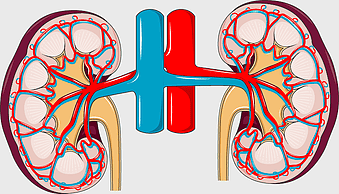

Human internal organs illustration, heart and lung anatomy, kidney and liver diagram, brain and stomach structure, medical organ chart, human body systems visual, educational anatomy graphics, PNG

- human internal organs illustration

- heart and lung anatomy

- kidney and liver diagram

- brain and stomach structure

- medical organ chart

- human body systems visual

- educational anatomy graphics

kidney anatomy, human kidney illustration, kidney cancer awareness, kidney organ diagram, renal system structure, medical kidney image, urinary system components -

kidney anatomy diagram, human kidney structure, retroperitoneal space illustration, blood vessels in kidneys, renal system visualization, medical kidney illustration, kidney cross-section analysis -